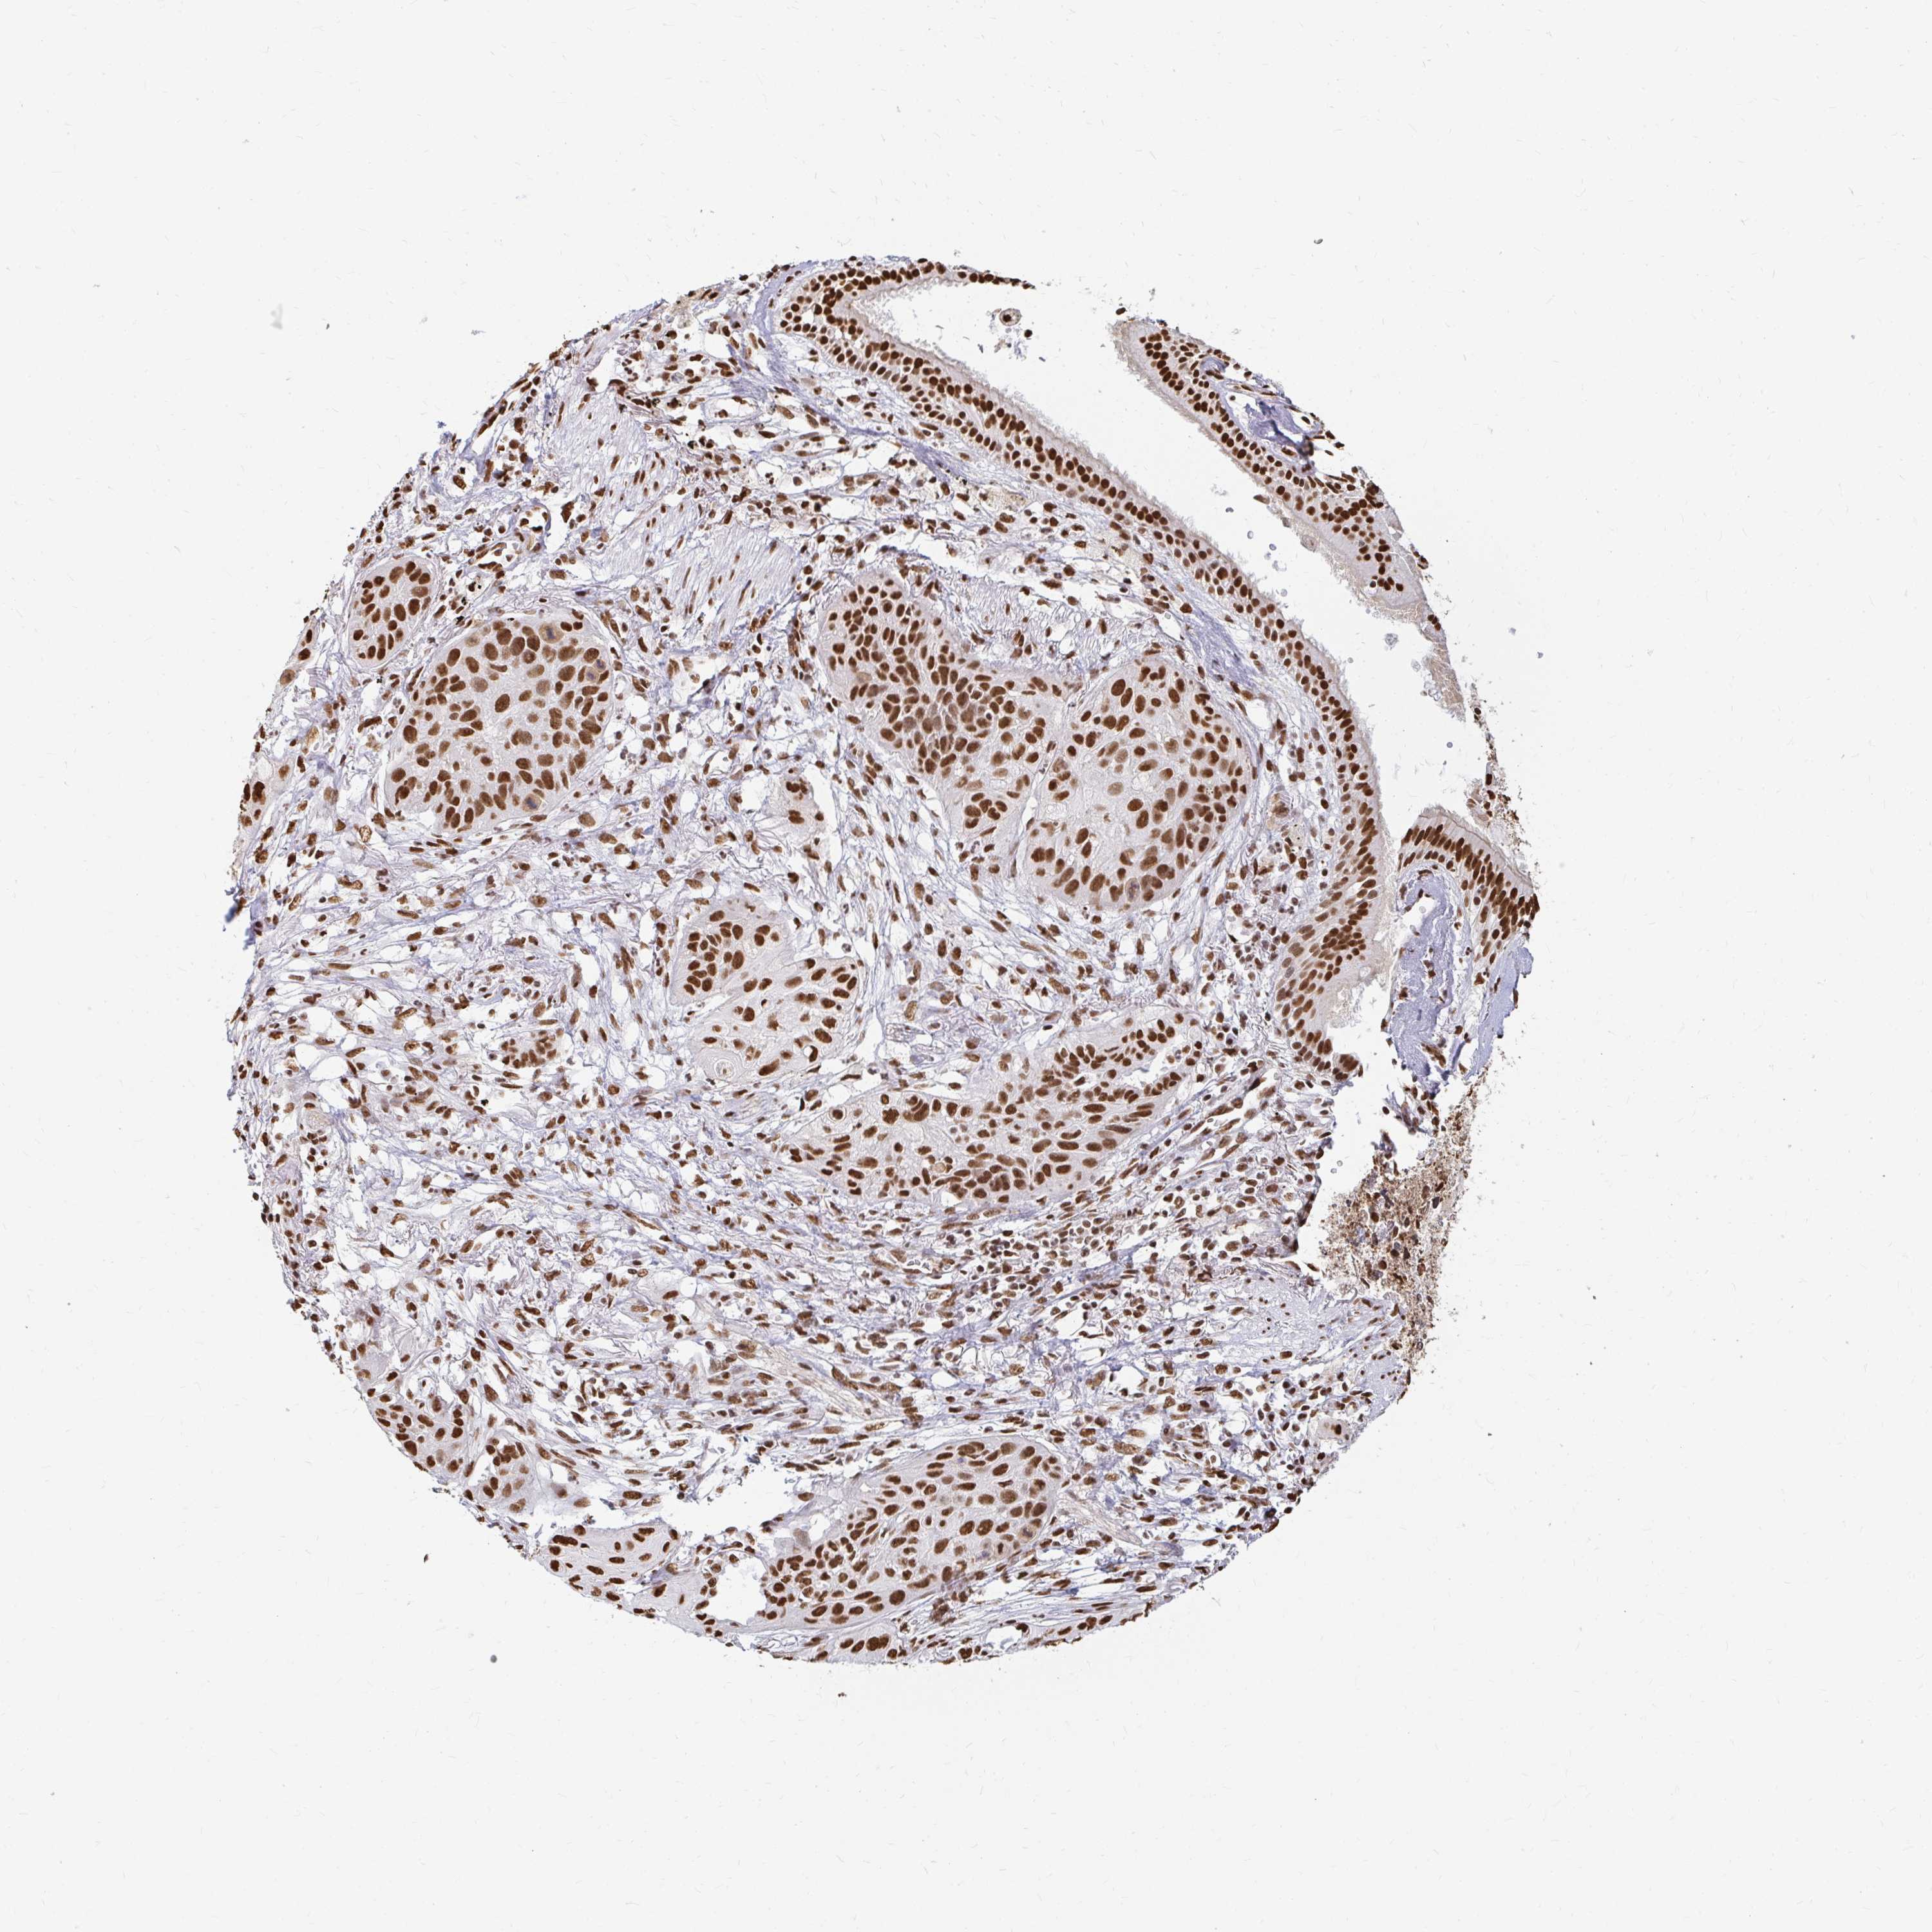

LUNG ADENOCARCINOMA (VALIDATION) - Interactive survival scatter ploti

The Survival Scatter plot shows the clinical status (i.e. dead or alive) for all individuals in the patient cohort, based on the same data that underlies the corresponding Kaplan-Meier plots. Patients that are alive at last time for follow-up are shown in blue and patients who have died during the study are shown in red.

The x-axis shows the expression levels (FPKM) of the investigated gene in the tumor tissue at the time of diagnosis. The y-axis shows the follow-up time after diagnosis (years). Both axes are complimented with kernel density curves demonstrating the data density over the axes. The top density plot shows the expression levels (FPKM) distribution among dead (red) and alive patients (blue). The right density plot shows the data density of the survived years of dead patients with high and low expression levels respectively, stratified using the cutoff indicated by the vertical dashed line through the Survival Scatter plot. This cutoff is automatically defined based on the FPKM cutoff that minimizes the p-score. The cutoff can be changed by dragging the vertical line or by entering a cutoff value in the square labeled "Current cut-off".

Under the Survival Scatter plot the p-score landscape (black curve; left axis) is shown together with dead median separation (red curve; right axis). Dead median separation is the difference in median mRNA expression between patients who have died with high and low expression, respectively. It is calculated as follows: median FPKM expression of dead patients with high expression - median FPKM expression of dead patients with low expression. This is intended to aid the user in visually exploring custom cutoffs and the associated p-scores and dead median separation.

Individual patient data is displayed and can be filtered by clicking on one or more of the category buttons on the top of the page. Categories describing expression level and patient information include: high, low, alive, dead, female, male and tumor stages. The scale of the x-axis can be toggled between linear and log-scale by clicking on the "x log" button. Mouse-over function shows TCGA ID, patient information and mRNA expression (FPKM) for each patient.

& Survival analysisi

Kaplan-Meier plots summarize results from analysis of correlation between mRNA expression level and patient survival. Patients were divided based on level of expression into one of the two groups "low" (under cut off) or "high" (over cut off). X-axis shows time for survival (years) and y-axis shows the probability of survival, where 1.0 corresponds to 100 percent.

HNRNPU is not prognostic in Lung Adenocarcinoma (validation)

Best expression cut offi

Based on the FPKM value of each gene, patients were classified into two groups and association between prognosis (survival) and gene expression (FPKM) was examined. The best expression cut-off refers the FPKM value that yields maximal difference with regard to survival between the two groups at the lowest log-rank P-value. Best expression cut-off was selected based on survival analysis .

When clicking on this number, the vertical dashed line indicating cut-off, the interactive survival plot, and the Kaplan-Meier curve will be adjusted to show results based on the best expression cut-off.

: 116.42

P scorei

Log-rank P value for Kaplan-Meier plot showing results from analysis of correlation between mRNA expression level and patient survival.

N/A

TCGA RNA samplesi

RNA-seq data is reported as average FPKM (number Fragments Per Kilobase of exon per Million reads), generated by the The Cancer Genome Atlas (TCGA) .

Normal distribution across the dataset is visualized with box plots, shown as median and 25th and 75th percentiles. Points are displayed as outliers if they are above or below 1.5 times the interquartile range. FPKM values of the individual samples are presented next to the box plot.

Average pTPM 150.9

Number of samples 105